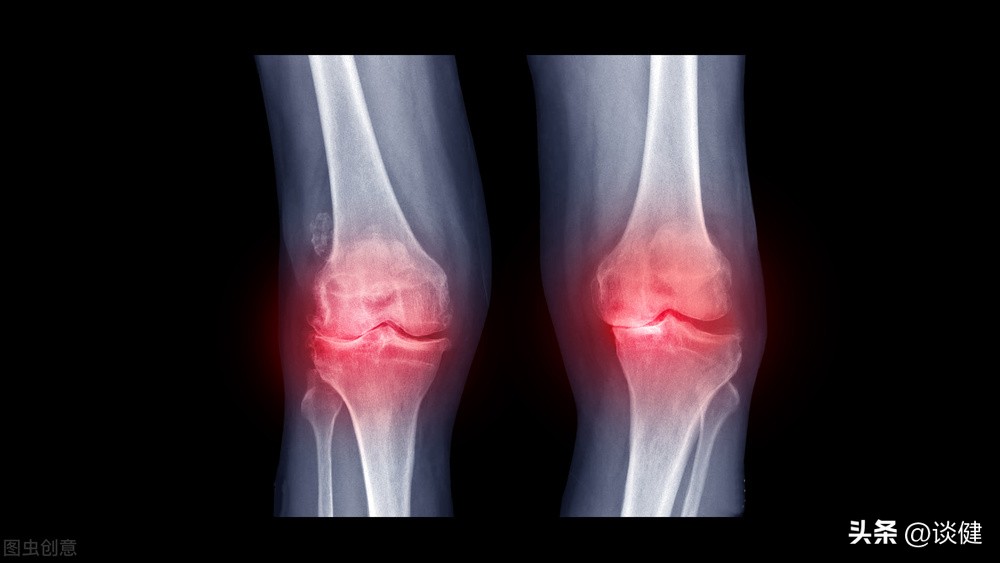

近期若自觉没走几步路就开始出现膝盖疼痛、偶尔蹲下时还会发出喀喀声,须留意可能为退化性膝关节炎的征兆。退化性膝关节炎的患者一般会感到关节疼痛,有时是间歇地隐隐作痛、活动受限,症状恶化到最后可能会失去活动能力。

退化性关节炎是中老年人常见的疾病。它是因为关节经年累月使用,或外来因素破坏,导致原本光滑的关节软骨产生屑片脱落,而出现发炎、疼痛的现象。退化性关节炎经常是中老年人冷风下的恶煞。大部分的人在初期时并不特别在意,认为老之将至罢了。医师强调,退化性关节炎不但使患者生活在疼痛中,更可能使行动变得不自如,因而应对此症多一分关心。 退化性关节炎早期并无明显症状,所以很容易被人忽略。因此,如果您是50岁以上银发族、肥胖的中年人(尤其妇女)、骨质疏松患者及有此症家族史的人,一旦出现关节僵硬、肿胀、疼痛等现象时,一定要速至医院检查、治疗,以免病情日益加重,或演变成慢性病,使行动受到限制。